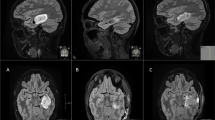

In preparation for a fifth attempt at local control, a neurosurgical iMRI (Siemens; Munich, Germany; 1.5 Tesla magnet on mobile track) was modified to perform an iMRI-assisted sarcoma resection of the lower extremity recurrence areas. Partnering with hospital staff engineers, the operating table was modified, following blueprint designs, using MRI-compatible materials (ie, brass or plastic polymer screws and washers, plastic or carbon fiber platform) to accommodate patient positioning that would allow for adequate observation of the musculoskeletal field (proximal leg, pelvis) in the mobile iMRI scanner (Fig. 1). After immediate preoperative contrast MR images were obtained for comparison purposes, the patient was brought to the iMRI surgical suite and positioned on the modified iMRI table. Using primarily short Tau inversion recovery (STIR) axial sequencing cuts, the anterior tumor and medial tumor recurrence locations (Fig. 2) were confirmed before incision, by comparing immediate preoperative images with the same intraoperative STIR sequences. After identifying the tumor location following initial dissection, the surgical field was imaged a second time to determine an appropriate resection margin surrounding each recurrence (Fig. 3). After tumor excision, both specimens were removed from the surgical field, but kept in the iMRI scanning field (Fig. 4). A third scan then was done to confirm adequate resection of the field and to confirm the specimen with appropriate tissue margins. Through intraoperative frozen section assessment and postoperative permanent section review, the two specimens were confirmed histologically to have negative margins. No contrast was used for reasons described by Gould et al. [9], detailed in the Discussion. To date, the patient has no evidence of disease at 37 months after MRI-assisted resection.

In our modified operative suite, (A) the table extension (to accommodate the extremity) is made of nonmagnetic objects, such as brass, polymers, and plastics. This modification can be removed easily and does not effect the use for future neurosurgery cases. (B) A technician attaches the table modification that allows the patient’s thigh or pelvis to enter the MRI scanner, with the patient in the supine position on the (C) modified table. (D) The MRI scanner is in a room adjacent to the operating room, and is moved to the operating room on (E) ceiling tracks thru a connecting door, with (F) all personnel, instruments, and equipment placed outside the gray peripheral line (magnetic field range) on the floor. An instrument count is performed before moving the instruments out of the magnetic field (any instrument unaccounted for is a potential projectile), while positive pressure flow prevents dirty airflow into the operating room suite while the magnet moves into position. (G) The scanner moves over the table extension, (H) encircling the extension where the operative extremity is positioned. With each MRI scan the machine takes 15 minutes to move along the tracks (and a reciprocal 15 minutes to exit the room), with 10 to 15 minutes used to count instruments with each cycle. In this case, we performed three separate image acquisitions, taking approximately 45 minutes for each cycle, accounting for 135 minutes of operating room time. In addition, the image acquisition and interpretation took approximately 15 minutes each time. Use of MRI for resection guidance accounted for nearly 3 hours of additional operative time.